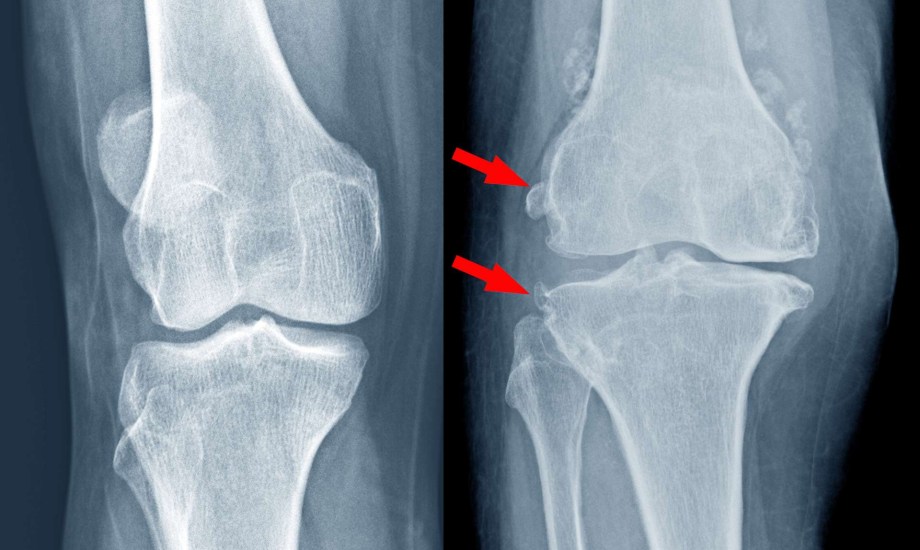

هشاشة العظام هي حالة مرضية تتميز بفقدان العظام لكثافتها وقوتها، ما يجعلها هشة وأقل قدرة على تحمل الضغط والصدمات، يحدث ذلك عندما يفقد الجسم كمية كبيرة من العظام أو عندما لا ينتج الجسم كمية كافية من العظام الجديدة.

هشاشة العظام لا تسبب عادة ألماً مباشراً، ولكنها تزيد من احتمالية الإصابة بالكسور التي قد تكون مصحوبة بآلام شديدة، عندما يحدث كسر في العظم المصاب بالهشاشة، يمكن أن يكون الألم شديداً وطويل الأمد، خاصةً إذا كان الكسر في العمود الفقري، يمكن أن تزداد الآلام في هذه الحالة بسبب الضغط على الأعصاب القريبة من العظم المكسور.

وتزيد هشاشة العظام من خطر الإصابة بالكسور، خاصةً في العمود الفقري، والورك، والمعصم.